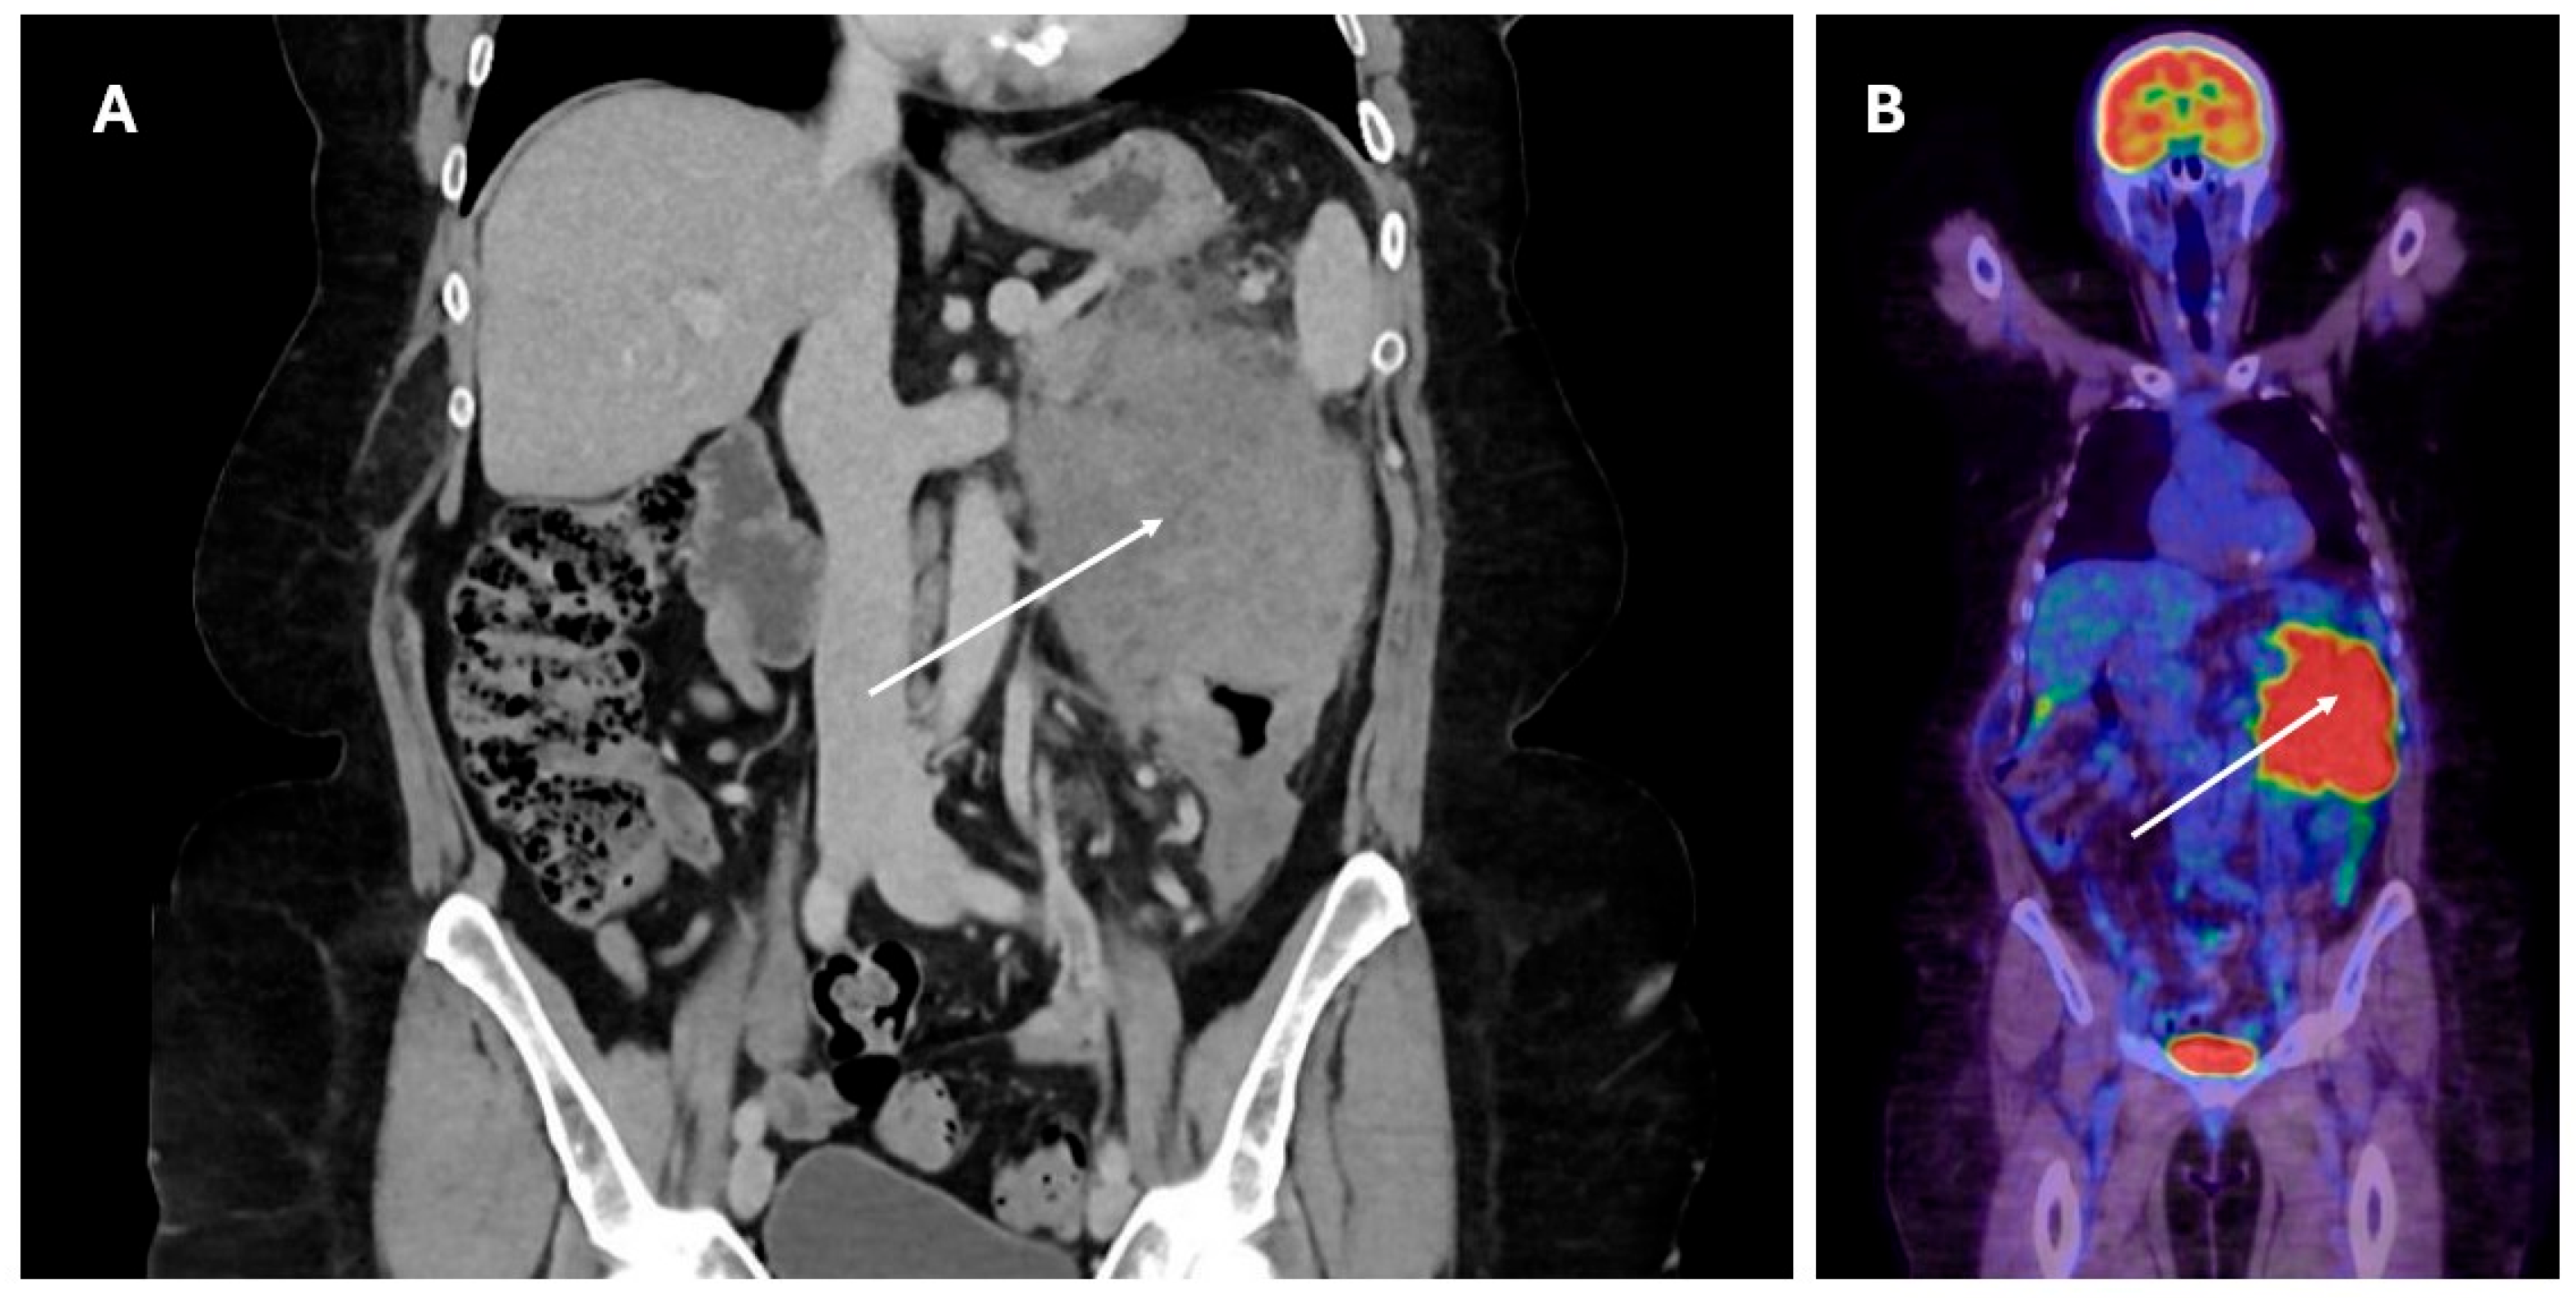

The significant majority (n = 24, 85.7%) of patients presented with visceral disease, with the remaining four (14.3%) patients presenting with nodal-only disease. Of those with visceral disease, the most involved organ was the bowel (n = 9, 37.5%), followed by the central nervous system (CNS) (n = 6, 25%) and soft tissue (n = 4, 16.7%). There were single (4.2%) cases involving the bone, bone marrow, lung, and spleen. Only one case involved the liver allograft itself. The mode of presentation reflected the involved organs, such that patients with bowel disease presented with a range of symptoms including abdominal pain, gastrointestinal bleeding, bowel obstruction, and loss of weight. Those with primary CNS disease presented with focal neurological symptoms or seizures. A typical diagnostic computed tomography (CT) scan and positron emission tomography (PET) scan for a patient presenting with PTLD involving bowel are presented in Figure 1, with the histology presented in Figure 2.

Figure 1.

PTLD presenting with mass (arrow) involving descending colon and small intestine visible on CT (panel (A)) with corresponding PET scan image (panel (B)).